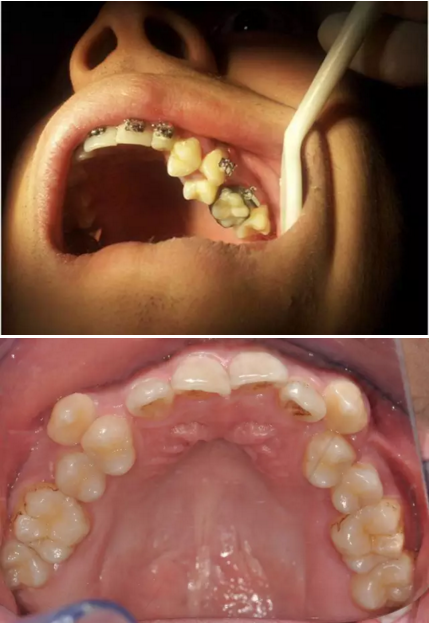

再看看逆襲的尖牙阻生。。。

小泥鰍

16.png

橫位

17.png

18.png

錯(cuò)位

19.png

大尺度異位

20.png